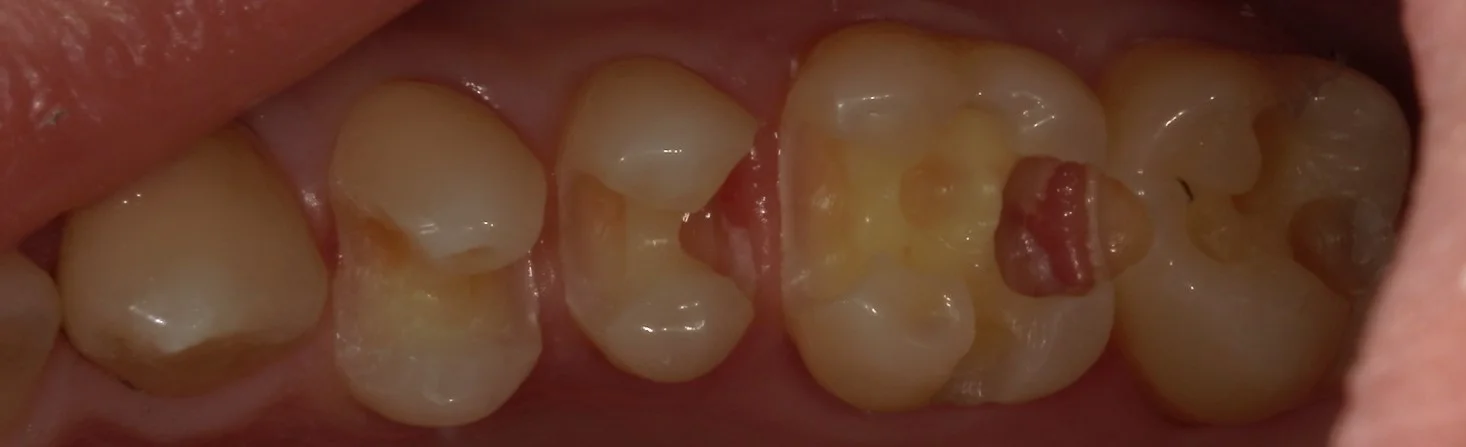

そして虫歯を取りきったのがこちらです。

中央2本が神経ギリギリの状態でした。

どちらも後ろ1/3~1/2は表層を残し、内面がほとんどすべてない状態になっています。

虫歯が歯茎よりも深い部分に入り込んでいました。

ここで歯茎を傷つけて出血させると、接着力が落ちてしまい、長期予後が期待できなくなってしまいますので気を付けて虫歯を取りきっていきます。